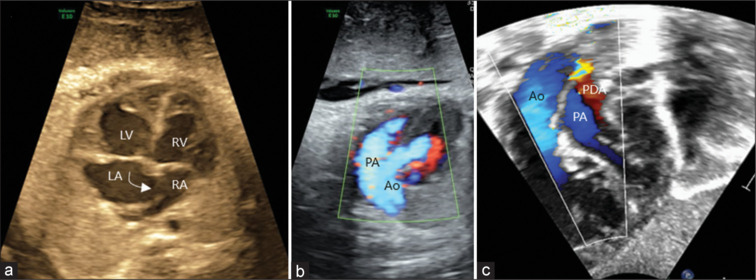

大多数产前发现d型大动脉转位并室间隔完整(TGA-IVS)的新生儿术前病程相对标准,但一些卵圆孔(FO)或动脉导管受限的患者出生后容易出现严重的低氧血症,在出生后数小时内死亡风险显著。含氧血和缺氧血混合不良会导致严重的紫绀和死亡。我们报告了两名产前诊断为TGA-IVS的新生儿,他们表现出明显的去饱和,需要紧急气囊房间隔造口术(BAS)。在这两个病人中,混合的结果是不充分的;导管支架植入必须恢复氧合。这些病例强调了产前识别TGA-IVS胎儿的高危特征的重要性,如限制性FO或导管收缩。尽管在解剖学上有足够的BAS,但这些婴儿中有一小部分混合不充分,可以在手术前通过导管支架植入进一步稳定。

Most neonates with prenatally detected d-transposition of great arteries with intact ventricular septum (TGA-IVS) have a relatively standard preoperative course, but some patients with restrictive foramen ovale (FO) or ductus arteriosus tend to have severe hypoxemia after birth, posing a significant risk of mortality in the first few hours after birth. Poor mixing of oxygenated and deoxygenated blood leads to severe cyanosis and death. We present two prenatally diagnosed neonates with TGA-IVS who presented with significant desaturation, necessitating emergency balloon atrial septostomy (BAS). In both patients, the resultant mixing was inadequate; ductal stenting had to be resorted to restore oxygenation. These cases highlight the importance of prenatal identification of high-risk features, such as restrictive FO or ductal constriction, in fetuses with TGA-IVS. A small proportion of these babies who have inadequate mixing despite an anatomically adequate BAS can be further stabilized before surgery by means of ductal stenting.